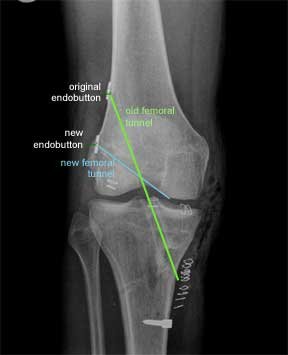

This is an X-ray of a patient who had a trans-tibial ACL reconstruction performed in another hospital. This was revised to a ‘more anatomic’ single bundle ACL, when it failed. The old femoral tunnel is highlighted in green and the new femoral tunnel is highlighted in blue.

This X-ray is from the front as before. The original endobutton was not removed. If you follow the line of the new femoral tunnel it is clear that it has been drilled from an antero- medial portal as the blue line points to two skin clips at this point.